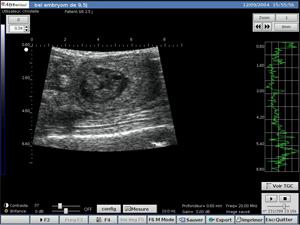

Embriones

- Visualización del desarrollo embrionario